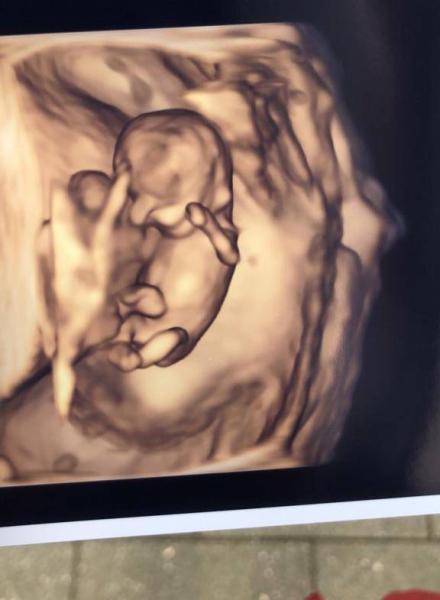

Ich war vorgestern bei der Pränataldiagnostik, um die "Zyste" an der Plazenta nochmal beurteilen zu lassen und ein frühes Organscreening zu machen. Für das Ersttrimesterscreening mit Nackenfaltenmessung war es in der 11. Woche noch zu früh, aber PAPP-A und freies Beta-HCG im Blut wurden schon mal abgenommen, den Termin zum richtigen Screening habe ich dann am 16.5. Bis dahin bin ich weiter krankgeschrieben, da alles noch so wacklig ist. Mein Arbeitgeber weiß noch nichts von der Schwangerschaft, ich hoffe bald endlich Bescheid geben zu können, dann werde ich ins Beschäftigungsverbot geschickt wegen Coronagefährdung. Wegen starker Übelkeit hätte ich so oder so bis jetzt nicht arbeiten können. Jetzt aber die vorerst guten Nachrichten: Baby ist super gewachsen, war für die 11. Woche normal entwickelt und hat wild gezappelt :D Magen, Harnblase und Nasenbein waren schon zu erkennen. Das Einzige, was auffiel, war ein kleiner, jetzt noch normaler Nabelbruch, der hoffentlich bis zum nächsten Mal verschwunden sein sollte. Ich habe ganz tolle Bilder bekommen, die haben dort Hightech-Ultraschallgeräte. Die Ärztin meinte, sie ist aufmerksam, aber nicht übermäßig besorgt. Nach dem Termin habe ich jetzt noch ein bisschen mehr Hoffnung, dass vielleicht doch alles gut geht und unser Kind soweit gesund ist. Wie geht es euch aktuell?

3D-Bild

Bild zu